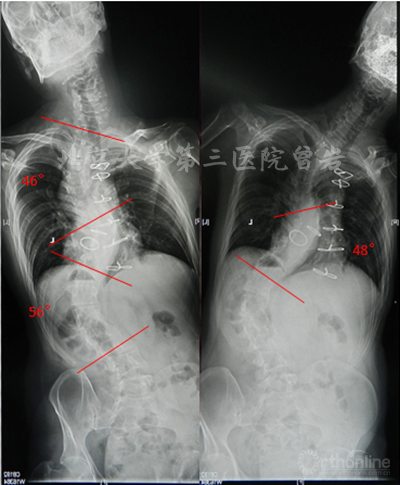

左右Bending X线(图6):左侧Bending上胸弯矫正至46°,胸腰弯矫正至56°;右侧Bending下胸弯矫正至48°。

图6